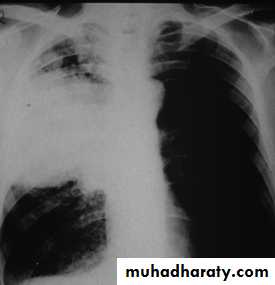

A chest X-ray is usually sufficient to confirm the clinical diagnosis of pneumonia.

In lobar pneumonia, a homogenous opacity localized to the affected lobe or segment usually appears within 12 – 18 hours of the onset of illness.

Chest X-ray helps in:• Differentiating CAP from other diagnosis

• Provide information about severity (cavitation and multilobar involvement)

• Detects complications (pleural effusion or abscess formation).

• It can occasionally suggest an aetiological agent (pneumatocoele in Staphylococcus aureus pneumonia).